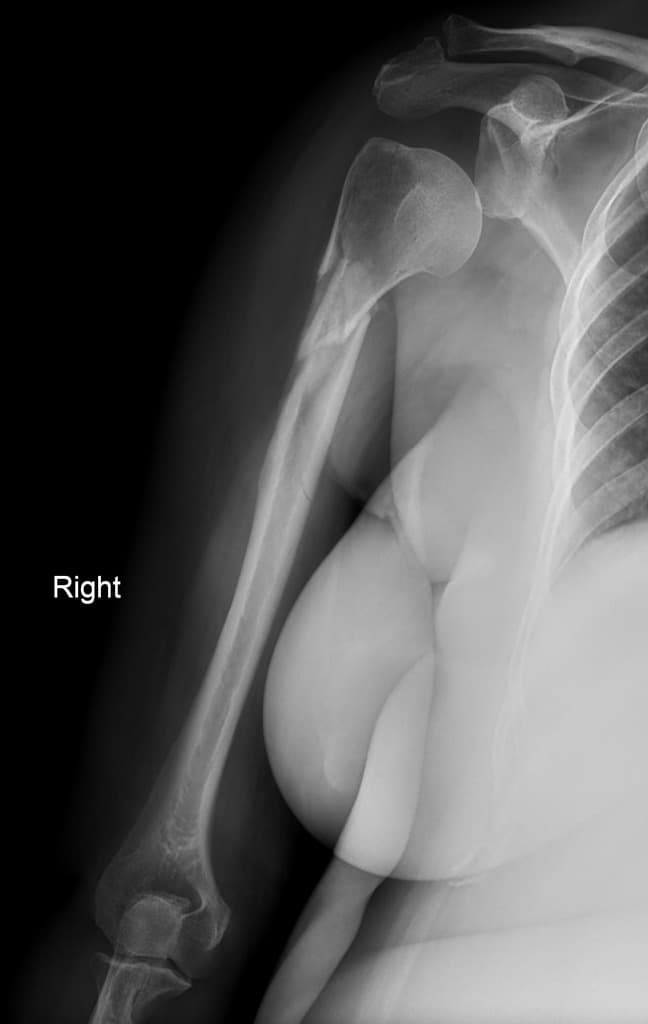

Anterior shoulder dislocation with Hill-Sachs lesion

Anterior shoulder dislocation with fracture of greater tuberosity of humeral head

Bilateral anterior shoulder dislocation

Comminuted humeral fracture